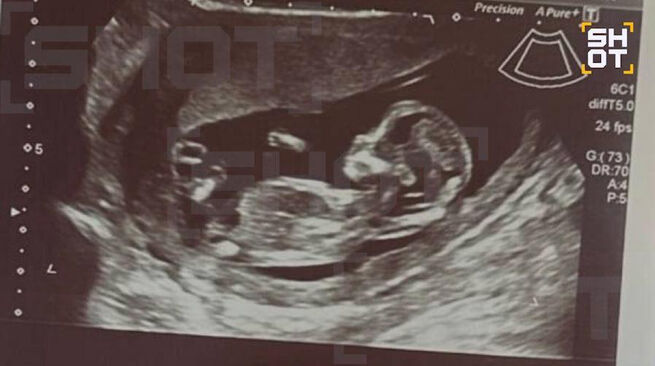

Telegram-канал SHOT сообщает, что сейчас девушка регулярно посещает врача, беременность протекает нормально.

Фото: Telegram / SHOT